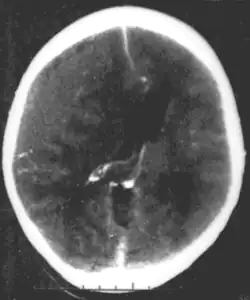

A number of infectious diseases can be transmitted congenitally (either before or at birth), and can cause serious neurodevelopmental problems, as for example the viruses HSV, CMV, rubella (congenital rubella syndrome), Zika virus, or bacteria like Treponema pallidum in congenital syphilis, which may progress to neurosyphilis if it remains untreated. Protozoa like Plasmodium[50] or Toxoplasma which can cause congenital toxoplasmosis with multiple cysts in the brain and other organs, leading to a variety of neurological deficits.